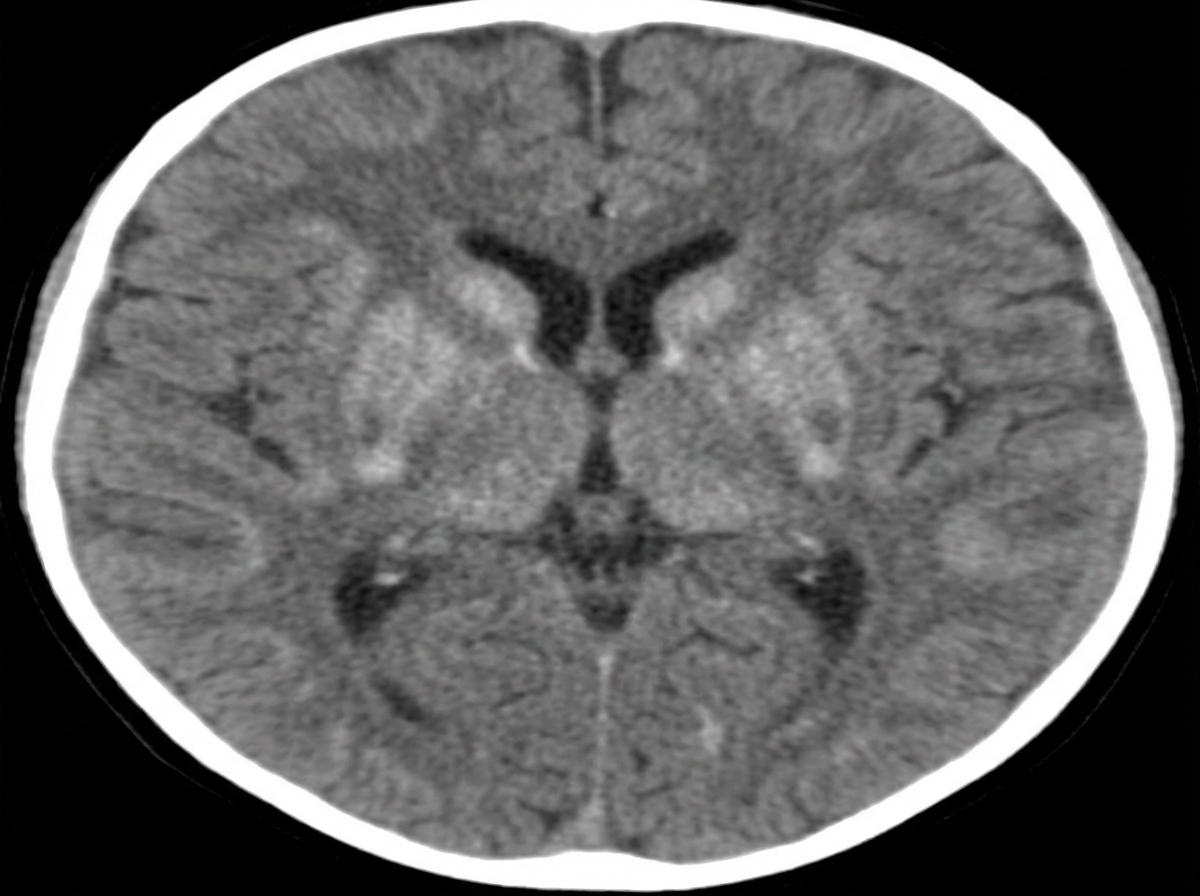

A 4-month-old child presents with excessive irritability and crying, unexplained hyperpyrexia, vomiting, and difficulty feeding for the last 15 days. On admission, the child has rigidity and visual inattentiveness. A CT scan of the brain shows specific findings. What is the probable diagnosis?

Explanation: ***Krabbe disease*** - Classic **infantile onset** at 3-6 months with **excessive irritability**, **hyperpyrexia**, and **feeding difficulties** strongly suggests Krabbe disease. - CT shows characteristic **hyperdense thalami** and **basal ganglia** with **periventricular white matter changes** and **rigidity** with **visual inattentiveness** are hallmark features. *Alexander disease* - Typically presents with **macrocephaly** and **developmental delay** rather than acute irritability and fever. - CT shows **frontal lobe predominance** with **white matter changes** and **Rosenthal fibers** on histology, not the thalamic hyperdensity seen here. *Metachromatic leukodystrophy* - Usually presents **later** (18-24 months) with **progressive motor regression** and **gait abnormalities**. - CT shows **symmetric periventricular demyelination** without the **hyperdense thalami** characteristic of Krabbe disease. *Adrenoleukodystrophy* - Typically affects **school-age boys** (4-8 years) with **behavioral changes** and **adrenal insufficiency**. - CT demonstrates **occipital-parietal white matter lesions** with **contrast enhancement**, distinct from the basal ganglia involvement in this case.